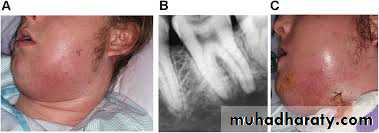

ACUTE ALVEOLAR ABSCESS:

Acute apical abscess.DEFINITION:

It is a localized collection of pus in the alveolar bone at the root apex following pulp death with extension of infection through apical foramen into periapical tissues.

Signs and Symptoms

There are local reactions like:Tenderness of tooth.

Severe throbbing pain.

Extra oral swelling.

Sinus tract in case of chronic exacerbation.

Systemic signs and

symptoms